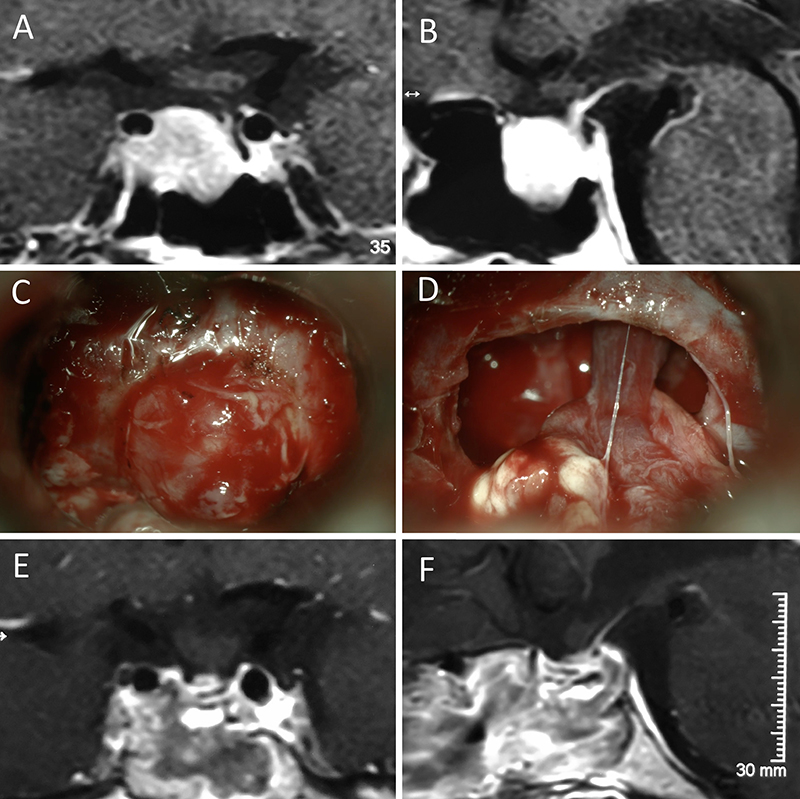

Figura 3: Macroadenoma no funcionante en un hombre de 64 años. El paciente presentó en el preoperatorio déficit visual que mejoró tras la cirugía. A-B: RM preoperatoria; C-D: intraoperatorio; E-F: RM postoperatoria.

Figura 4: Macroadenoma no funcionante en mujer de 32 años. La paciente presentó en el preoperatorio déficit visual que mejoró tras la cirugía. A-B: RM preoperatoria; C-D: intraoperatorio; E-F: RM postoperatoria.